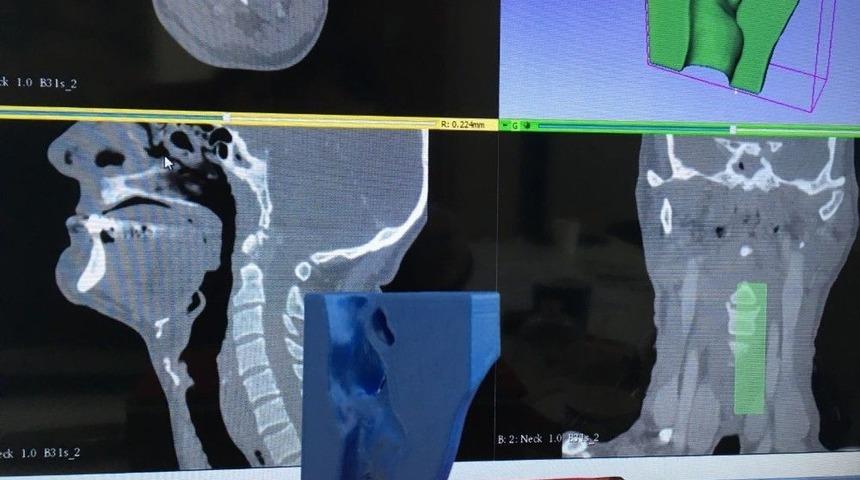

Isparta Süleyman Demirel Üniversitesinde kemik, kas, kitle ve yumuşak dokuların plastik katı modelleri üretildi.Isparta’da Süleyman Demirel Üniversitesi (SDÜ) Mühendislik, Tıp, Diş Hekimliği Fakültesi öğretim üyeleri, bilgisayarlı tomografi ve manyetik rezonans ile elde edilen verileri üç boyutlu yazıcı (3D) teknolojisi kullanarak kemik, kas, kitle, implant ve yumuşak dokuları plastik katı modele dönüştürdü. Bazı modeller için patent başvurusu da yapıldı.Konuyla ilgili bir açıklama yapan Yrd. Doç. Dr. Mehmet Mahir Sofu, hastalık tanı ve teşhisinde kullanılan bilgisayarlı tomografi (CT) ve manyetik rezonans (MR) ile elde edilmiş verilerin çeşitli yazılımlar ile işlenerek kemik, kas, kitle ve yumuşak dokuların katı modellere dönüşümünü sağladıklarını bildirdi. Sofu, bu gelişmenin tıbbi çalışmalara farklı bir boyut kazandıracak hamle olduğunu ifade etti.SDÜ Tıp Fakültesi Öğretim Üyesi Yrd. Doç. Dr. Meriç Ünal ise, disiplinlerarası gerçekleştirilen bilimsel çalışmanın önemine vurgu yaparak, “Tıbbi görüntüleme tekniklerinden MR ve CT verilerini kullanarak üç boyutlu yazıcıdan elde edilen katı modellerle ortopedide özellikle dizilim bozukluklarının düzeltilmesinin analizi, cerrahi operasyonların planlamasında, tümör olgularında yapılacak rekonstrüktif cerrahilerin planlamasında ve operasyon süresinin düşürülmesinde önemli rolünün olduğu kanıtlanmıştır” dedi.“Ameliyat başarısını artırmaktadır”Diş Hekimliği Fakültesi Öğretim Üyesi Prof. Dr. Süha Türkaslan ve Doç. Dr. Yavuz Fındık, yaptıkları ortak açıklamada şu bilgileri paylaştılar:“Üç boyutlu görüntüleme, yenilikçi üç boyutlu yazıcı (3D) teknolojisi ve bilgisayar destekli tasarım ve imalât (CAD- CAM) teknolojileri klasik diş hekimliği uygulamalarının birçoğunu dijital diş hekimliğine kaydırdı. Diş hekimliğinin her alanına göre bu teknolojilerden farklı şekilde faydalanıyoruz. Mesela çene cerrahisi alanında üç boyutlu teknolojileri, implant ihtiyacı olan ancak implant yerleştirilecek bölgenin hayati dokulara yakın olduğu için riskli olduğu veya yetersiz kemik seviyesine sahip hastalarda kullanıyoruz. Böylece hem doğru teşhis ve implant planlaması yapıyor hem de cerrahi süresini oldukça kısaltan, 3D’de ürettiğimiz implant rehberlerini hazırlayabiliyoruz. Çene ameliyatlarında, ameliyat öncesinde alınan modeller ile model cerrahisi yapılabilmekte böylece ameliyat süresi önemli oranda azalmaktadır. Çenelerde meydana gelen defektlerde de aynı şekilde üç boyutlu modeller ile ameliyat öncesi tüm planlamaları yapılabilmekte bu da ameliyat başarısını artırmaktadır.”“Eğitici bir görsel”Sağlık Hizmetleri Meslek Yüksek Okulu Tıbbi Hizmetler ve Teknikler Bölümü Öğretim Üyesi Yrd. Doç. Dr. Hatice Akpınar ise, “CT datalarını kullanarak yenilikçi 3D yazıcı teknolojisi ile üç boyutlu çıktısını aldığımız larinks anatomisi modellemesi, nazofarenks kanserli bir hastada anestezi yönetimi, ameliyat tekniği ve daha sonra hastanın nefes almasını sağlayacak trakeostomi kanülünün yerleşim yerinin tespitinde doğru karar verilmesinde faydalı olmuştur. Ayrıca materyal hem cerrahi hem anestezi öğrencileri için eğitici bir görseldir” dedi.“Model için patent başvurusunda bulunduk”SDÜ Tıp Fakültesi Öğretim Üyesi Yrd. Doç. Dr. Giray Kolcu ve Uzman Diştabibi M. İnci Başer Kolcu, çalışmaya ilişkin şu açıklamayı yaptılar:“Rejeneratif Endodontik Tedavilerin Uygulama Modeli çalışmamızda üç boyutlu yazıcı teknolojisi kullanarak 54 adet apeksi kapanmamış santral dişin katı modelini oluşturduk. Bu modelleri daha sonra rejeneratif endodontik tedavilerin eğitimi sırasında öğrencilerin konuyla ilgili psikomotor becerilerini geliştirebilecekleri bir eğitim materyali oluşturduk. Geliştirilen materyalin denemelerinin oldukça başarılı olması sonucunda modelin patent başvurusunu gerçekleştirdik.”“Medikal alandaki teknolojik yenilikçi gelişmeler SDÜ’de gerçekleşiyor”Yrd. Doç. Dr. Mehmet Mahir Sofu, bu uygulamaların profesyonel bir ekipmanla klinik ve cerrahi uygulamalarda kullanılabileceğini dile getirdi. Sofu, üç boyutlu uygulamaları ile tıbbi cihazların performansını arttırıcı modifiye çalışmaların ve cerrahi uygulamalarda kullanılan cerrahi aletlerin yenilikçi tasarımı ve prototip imalâtlarının da yapılabileceğini ifade etti. Sofu, Türkiye’de sayılı üniversitelerde uygulanan bu yöntemle medikal alandaki teknolojik yenilikçi gelişmelerin SDÜ’de de gerçekleştiğini vurguladı. Aynı zamanda bu yöntemin eğitim materyalleri üretiminde de kullanabileceğini söyleyen Sofu, SDÜ’de her birim için benzer çalışmalara destek verebileceklerini sözlerine ekledi.